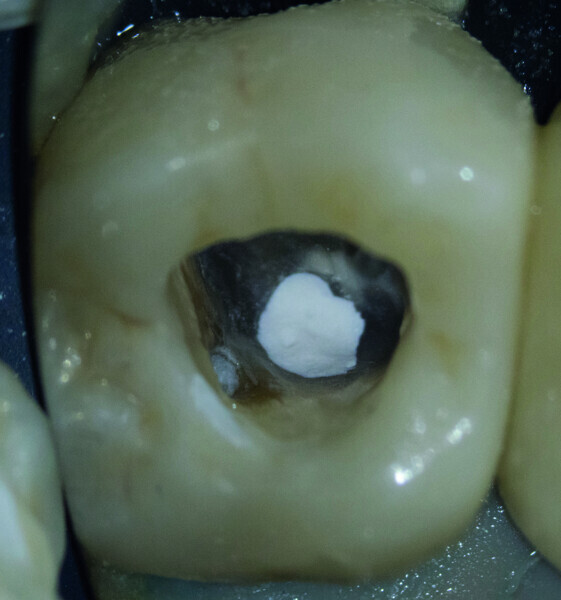

Fig. 6 : Le ciment hydraulique à base de silice après sa prise complète.

Fig. 7 : L’excès de ciment a été éliminé autant que possible.

Fig. 8 : Dentine et ciment obturés avec G Premio BOND.